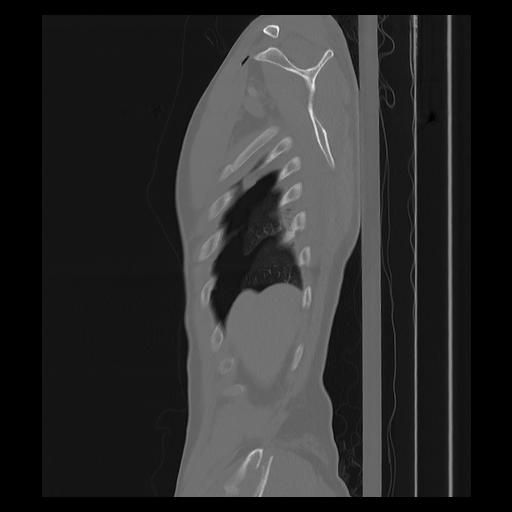

33 PULMON,CE,Sagittal,3.000,PULMON,Sagittal,